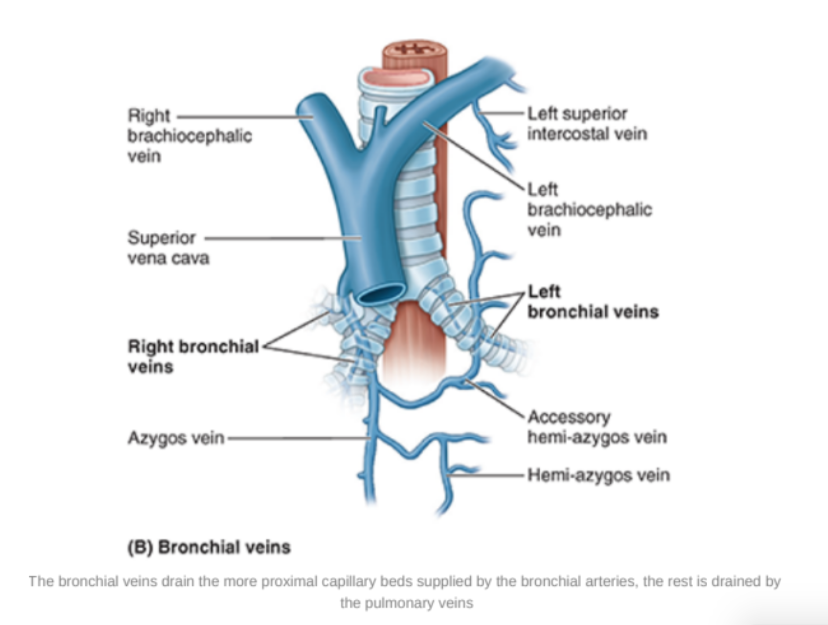

Bronchial veins —

Right bronchial vein drains into the azygos vein

Left bronchial vein drains into the accessory hemi-azygos or left superior intercostal vein

Bronchial veins also receive some blood from esophageal veins